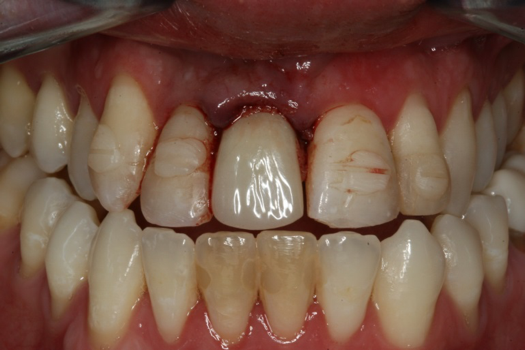

Case 2. Smile Zone Implant: Single Maxillary Central Incisor

Providing single-tooth restorations in the smile zone can be challenging; considerations for implant dentistry for a single maxillary incisor can be even more challenging. For this case, the digital workflow considerations were not much different from the previous case; radiographs, photography, and analog impressions were used. The patient was given alternative treatment options. He chose a single implant and final zirconia with cutback for porcelain application. The patient was advised about his surrounding vintage dentistry and told he should consider all maxillary anterior teeth, Nos. 6 through 11, be planned for better function and esthetics. The patient had the final say, which allowed the laboratory and the author to finalize the treatment plan with the definitive restoration.

Properly planning this case with digital dental technology offered a large quantity and quality of diagnostic information. Using the dental laboratory software to merge the entire 3D data set helped to predict the best outcome after the digital proposals for the implant abutment and final crown. The patient had been involved with implant dentistry and understood the value of technology available.

Figure 6 and Figure 7 depict a mature smile with many implant restorations. An analog impression was sent to the laboratory. The impression was scanned by the laboratory, a model was created virtually, and the implant dimensions and position were defined. The 3D surgical guide was fabricated (Figure 8), allowing the patient to receive his therapy swiftly and predictably. Tooth No. 8 was extracted, and the implant was placed and immediately loaded with an acrylic provisional treatment crown (Figure 9). The screw-retained treatment crown was fabricated in-office from a previously completed diagnostic wax-up.

Fig 6. Image of the patient’s mature smile.

Figure 6

Fig 9. Surgery day with immediately loaded implant and treatment crown.

Figure 9